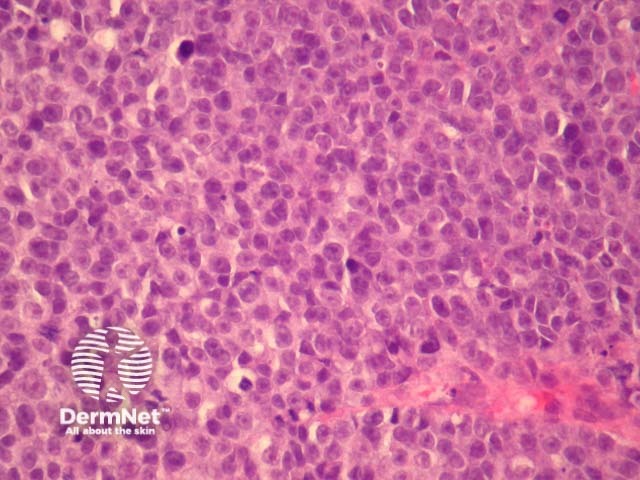

Cutaneous metastasis of melanoma can cause diagnostic confusion. The metastatic melanoma may invade the dermis or subcutis and form a nodular tumour mass without invasion of the overlying epidermis (figure 1). The pattern of growth may mimic a benign intradermal naevus at low power (figure 1) but at high power examination the nuclear atypia is usually obvious, there may be mitoses and there is minimal evidence of maturation (decrease in cell size) with descent in the dermis (figure 2). Usually the lack of epidermal involvement is a good clue the tumour is a metastasis from another site but sometimes the metastasis may invade the epidermis and closely simulate a primary melanoma.

Rarely, melanoma which has metastasised to the dermis may closely mimic a blue naevus (blue naevus-like melanoma, figures 3,4). This can cause considerable diagnostic difficulty and be impossible to correctly recognise without clinical information.

Figure 1

Figure 2

Figure 3

Figure 4